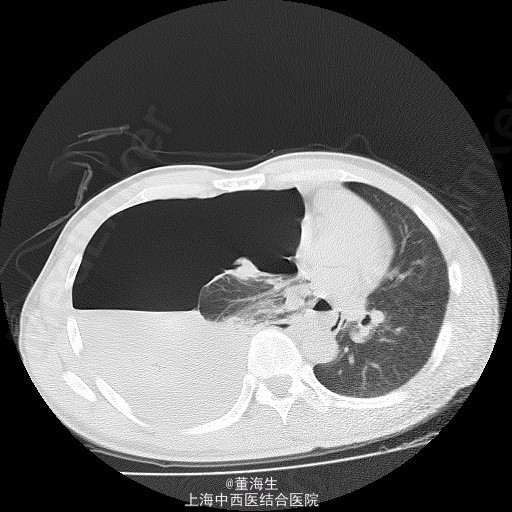

患者,男,39岁。 1.主诉、现病史:患者因为“突发胸闷1日”入院。患者入院当日1:00突觉胸闷,至约16:00来院就诊,辅查胸部CT后如附图1,附图2。既往无类似发作史。 2.查体:患者神清,精神状态良好,生命体征平稳,无气促。右肺听诊呼吸音消失,左侧正常。 3.辅助检查:胸部CT表现如附图1,附图2,血常规提示120g/L,血红蛋白压积正常。 4.诊断:右侧自发性血气胸。 5.处理方案: ①入院后明确诊断,即刻取右侧锁中线第2肋间行胸腔闭式引流。置入8F一次性引流导管一根(该导管头端卷曲,有多个侧孔),导管接水封瓶。静脉给予抗生素及凝血酶,床边心电监护。 ②闭式引流后3小时内引流大量气泡并引流血性液1100ml,即刻复查血常规提示Hgb102g/L。 ③引流3小时后观察引流液不再明显增加,至第二日晨共1400ml血性液,复查血常规仍为102g/L。 ④引流第二日起引流液色逐渐转至浆液性,至入院第6日共引出液体2100ml,负压波动消失,每日引流量少于100ml。予夹闭引流管。 ⑤夹管24小时后复查胸部CT,结果见附图3,附图4。当日予拨除胸腔闭式引流。 6.随访复查:出院后1周,门诊复查胸片及胸水B超,提示无气胸及液胸。 7.分享病例的体会: 实习时老师教导,每小时胸引>200ml血性液,应急诊行剖胸探查。该病例实际治疗时因读片提示胸腔大量积液,保守估计该有1500ml左右,且发病至入院已约15小时,且患者生命体征平稳。故治疗时采取的思路为先放尽积液再计算单位时间内引流量,同时密切观查患者生命体征变化。 此病例没有盲从缺少先决条件的临床条例,免除了患者的手术痛苦。 是否得当请广大同行指正!